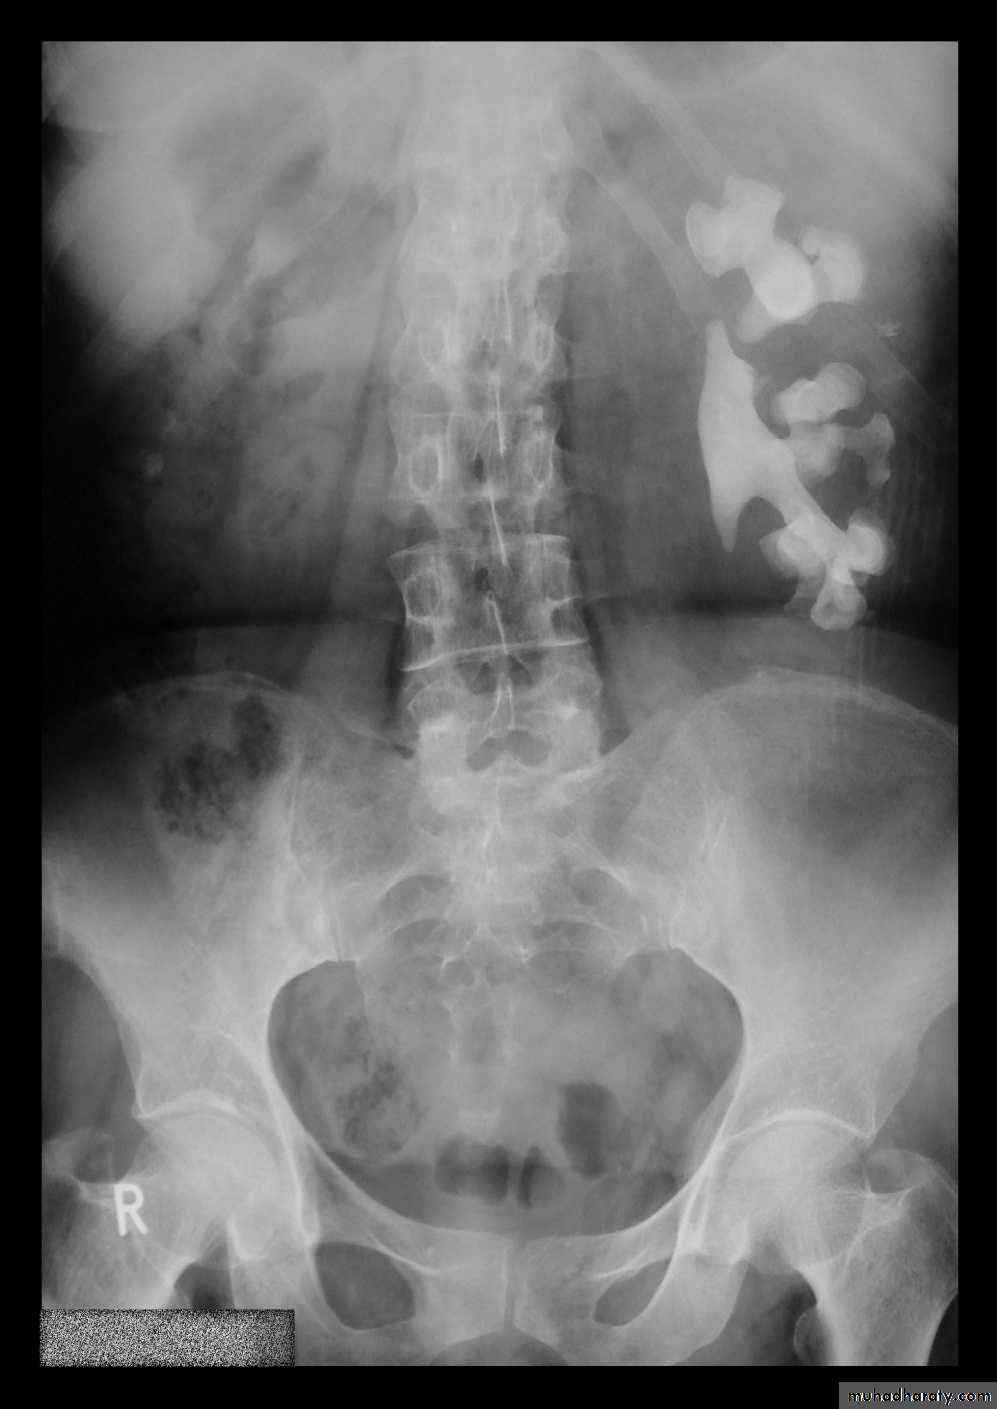

radiographic appearance in bladder exstrophy. It describes wide midline separation of the pubic bones.Bladder exstrophy (also known as ectopia vesicae) refers to a herniation of the urinary bladder through an anterior abdominal wall defect. The severity of these defects is widely variable.

Horse shoe kidney